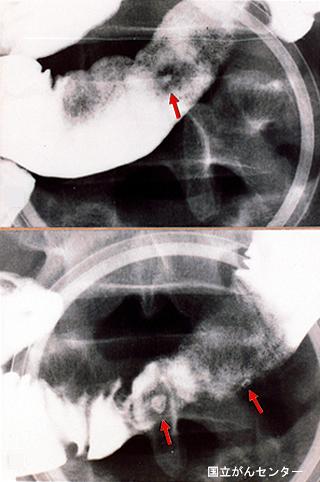

Ulcera de Intestino Delgado con el síndrome múltiple (supuesto síndrome de Churg - Strauss) que acompañan pirexia, tumor y heces sanguíneas

Tokyo Pref., Centro Nacional de curaciones de Cáncer, Hospital Central y Centro Kyusyu de Curaciones de Cáncerc

Enfermedad Inflamatoria - Ulcerativa/otros

intestino delgado/ileón

Rayos X

1 - 9